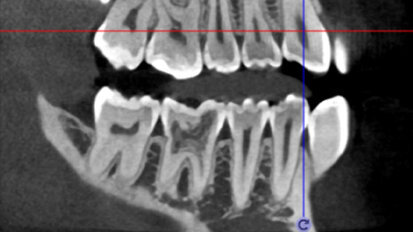

Vědci vyvinuli model pro automatickou lokalizaci mandibulárních kanálků

ESPOO, Finsko: Před zaváděním implantátu musí zubní lékaři nejprve lokalizovat mandibulární kanálek, což se obvykle dělá s pomocí CBCT ...

3D technologie v diagnostice a léčbě endodontických onemocnění

Technologie spjatá s endodontickou terapií prošla v posledních letech opravdovou revolucí. Po dlouhá léta byly využívány jako základ pro ...